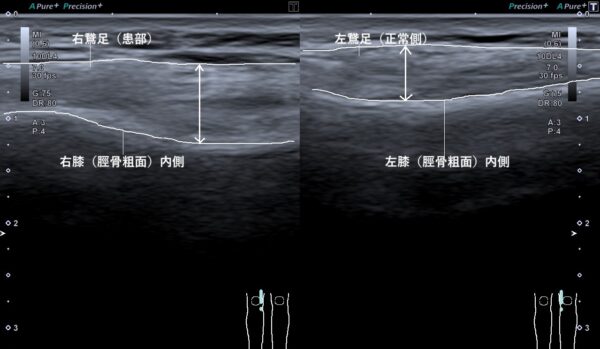

超音波画像観察を行うと右鵞足部の筋肉が傷んでいて、左と比較すると明らかに腫れていました(画像、矢印の長さの比較)。